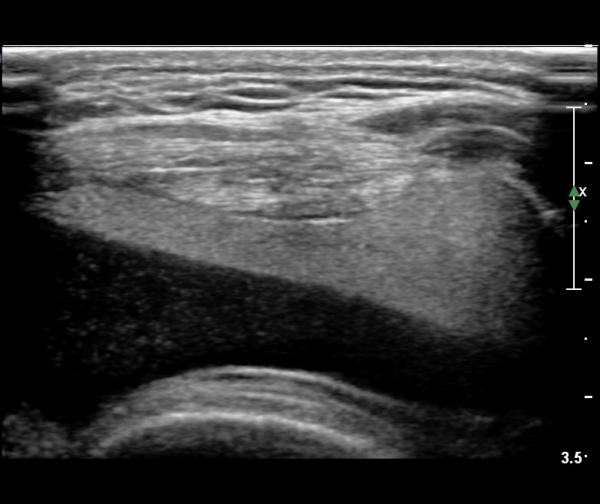

¹«¸­ ÃøºÎ Á¾´Ü¸é°Ë»ç¿¡¼­ °í¿¡ÄÚ ¼ö¾×Àý·ù°¡ °üÂûµÊ( »çÁø 1).